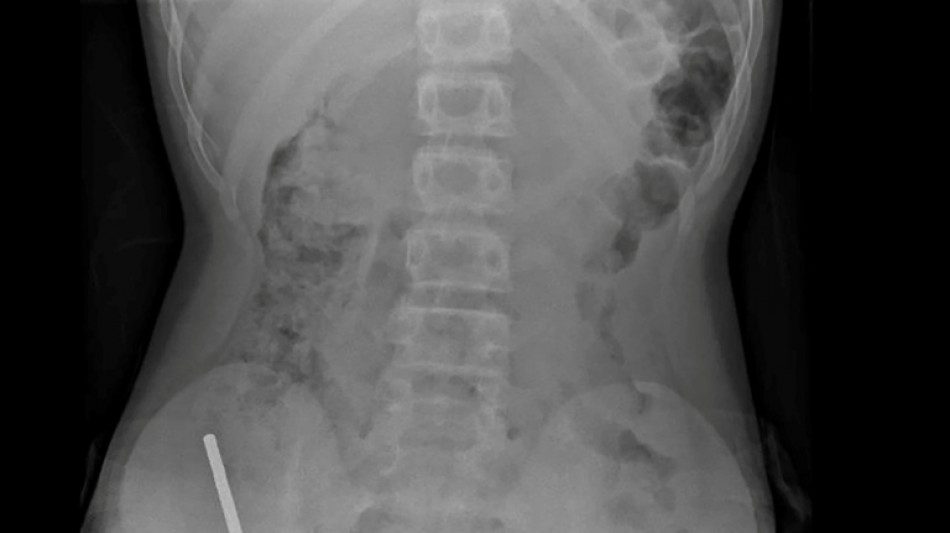

Nouvelle-Zélande: un adolescent opéré après avoir ingéré près de 100 aimants achetés sur Temu / Photo: © NEW ZEALAND MEDICAL JOURNAL (NZMDJ)/AFP

En Nouvelle-Zélande, un adolescent de 13 ans s'est vu retirer plusieurs parties nécrosées de ses intestins après avoir avalé près d'une centaine d'aimants achetés en ligne sur le site Temu, a rapporté vendredi une revue médicale.

"Il avoué avoir ingéré entre 80 et 100 aimants puissants au néodyme, de 5x2mm environ, une semaine plus tôt", indique un rapport des médecins de l'hôpital de cet hôpital, publié dans le New Zealand Medical Journal (NZMJ).

Les médecins ont déclaré que la pression exercée par les aimants avait provoqué une nécrose dans quatre zones de l'intestin grêle et du gros intestin du garçon.

Il a été opéré afin que l'on lui retire les aimants et les tissus nécrosés, et il a pu rentrer chez lui après huit jours à l'hôpital.